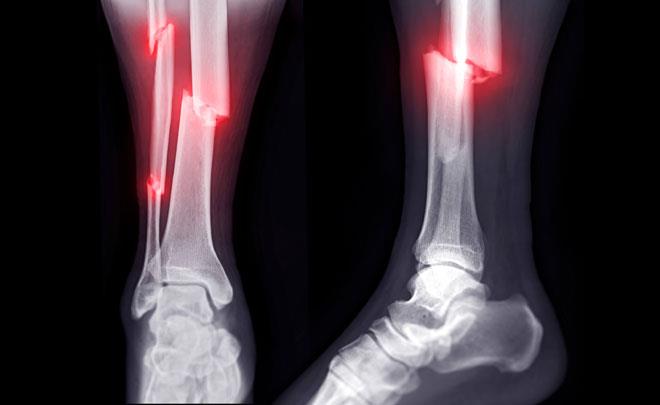

‌شکاوی ئێسک تەنها بە نەشتەرگەری چاک دەبێتەوە؟

هەموو شکانەکان بە نەشتەرگەری چارەسەر ناکرێن، بەڵکو زۆربەیان دەتوانن بەبێ نەشتەرگەری چاک ببنەوە، چارەسەرەکە بەندە بە جۆری شکانەکە و شوێنی شکانەکەی و توندییەکەی و ئایا ئێسکەکان جێگیرن یان نا.

- جێگیرکردنی ناوەوە: پلێت، برغو، یان کانزاییەک کە لە ناوەوە دادەنرێت بۆ ئەوەی پارچە ئێسکەکان بەیەکەوە بگرن.

- جێگیرکردنی دەرەکی: چوارچێوەیەکە لە دەرەوەی جەستە کە بەستراوەتەوە بە ناو ئێسک، بەزۆری بۆ شکانی ئاڵۆز یان کراوە بەکاردێت.

- بەزۆری پێویستە نەشتەرگەری بکرێت ئەگەر:

1- کۆتاییەکانی ئێسکەکان لەیەکتر دوور بن.

2- شکانەکە جومگەیەک دەگرێتەوە.

3- چەندین پارچە هەیە (شکانی بچووک).

4- شکانەکە کراوەیە واتە  ئێسکەکە لە پێستەکەوە هاتووەتە دەرەوە.

- کەواتە، زۆرێک لە شکانەکان (وەک شکانی سادەی مەچەک یان پێ) بە باشی چاک دەبنەوە تەنها بە بێ جووڵەکردن، لەکاتێکدا هەندێکی تر (وەک شکانی قاچ) بەزۆری پێویستیان بە نەشتەرگەرییە.